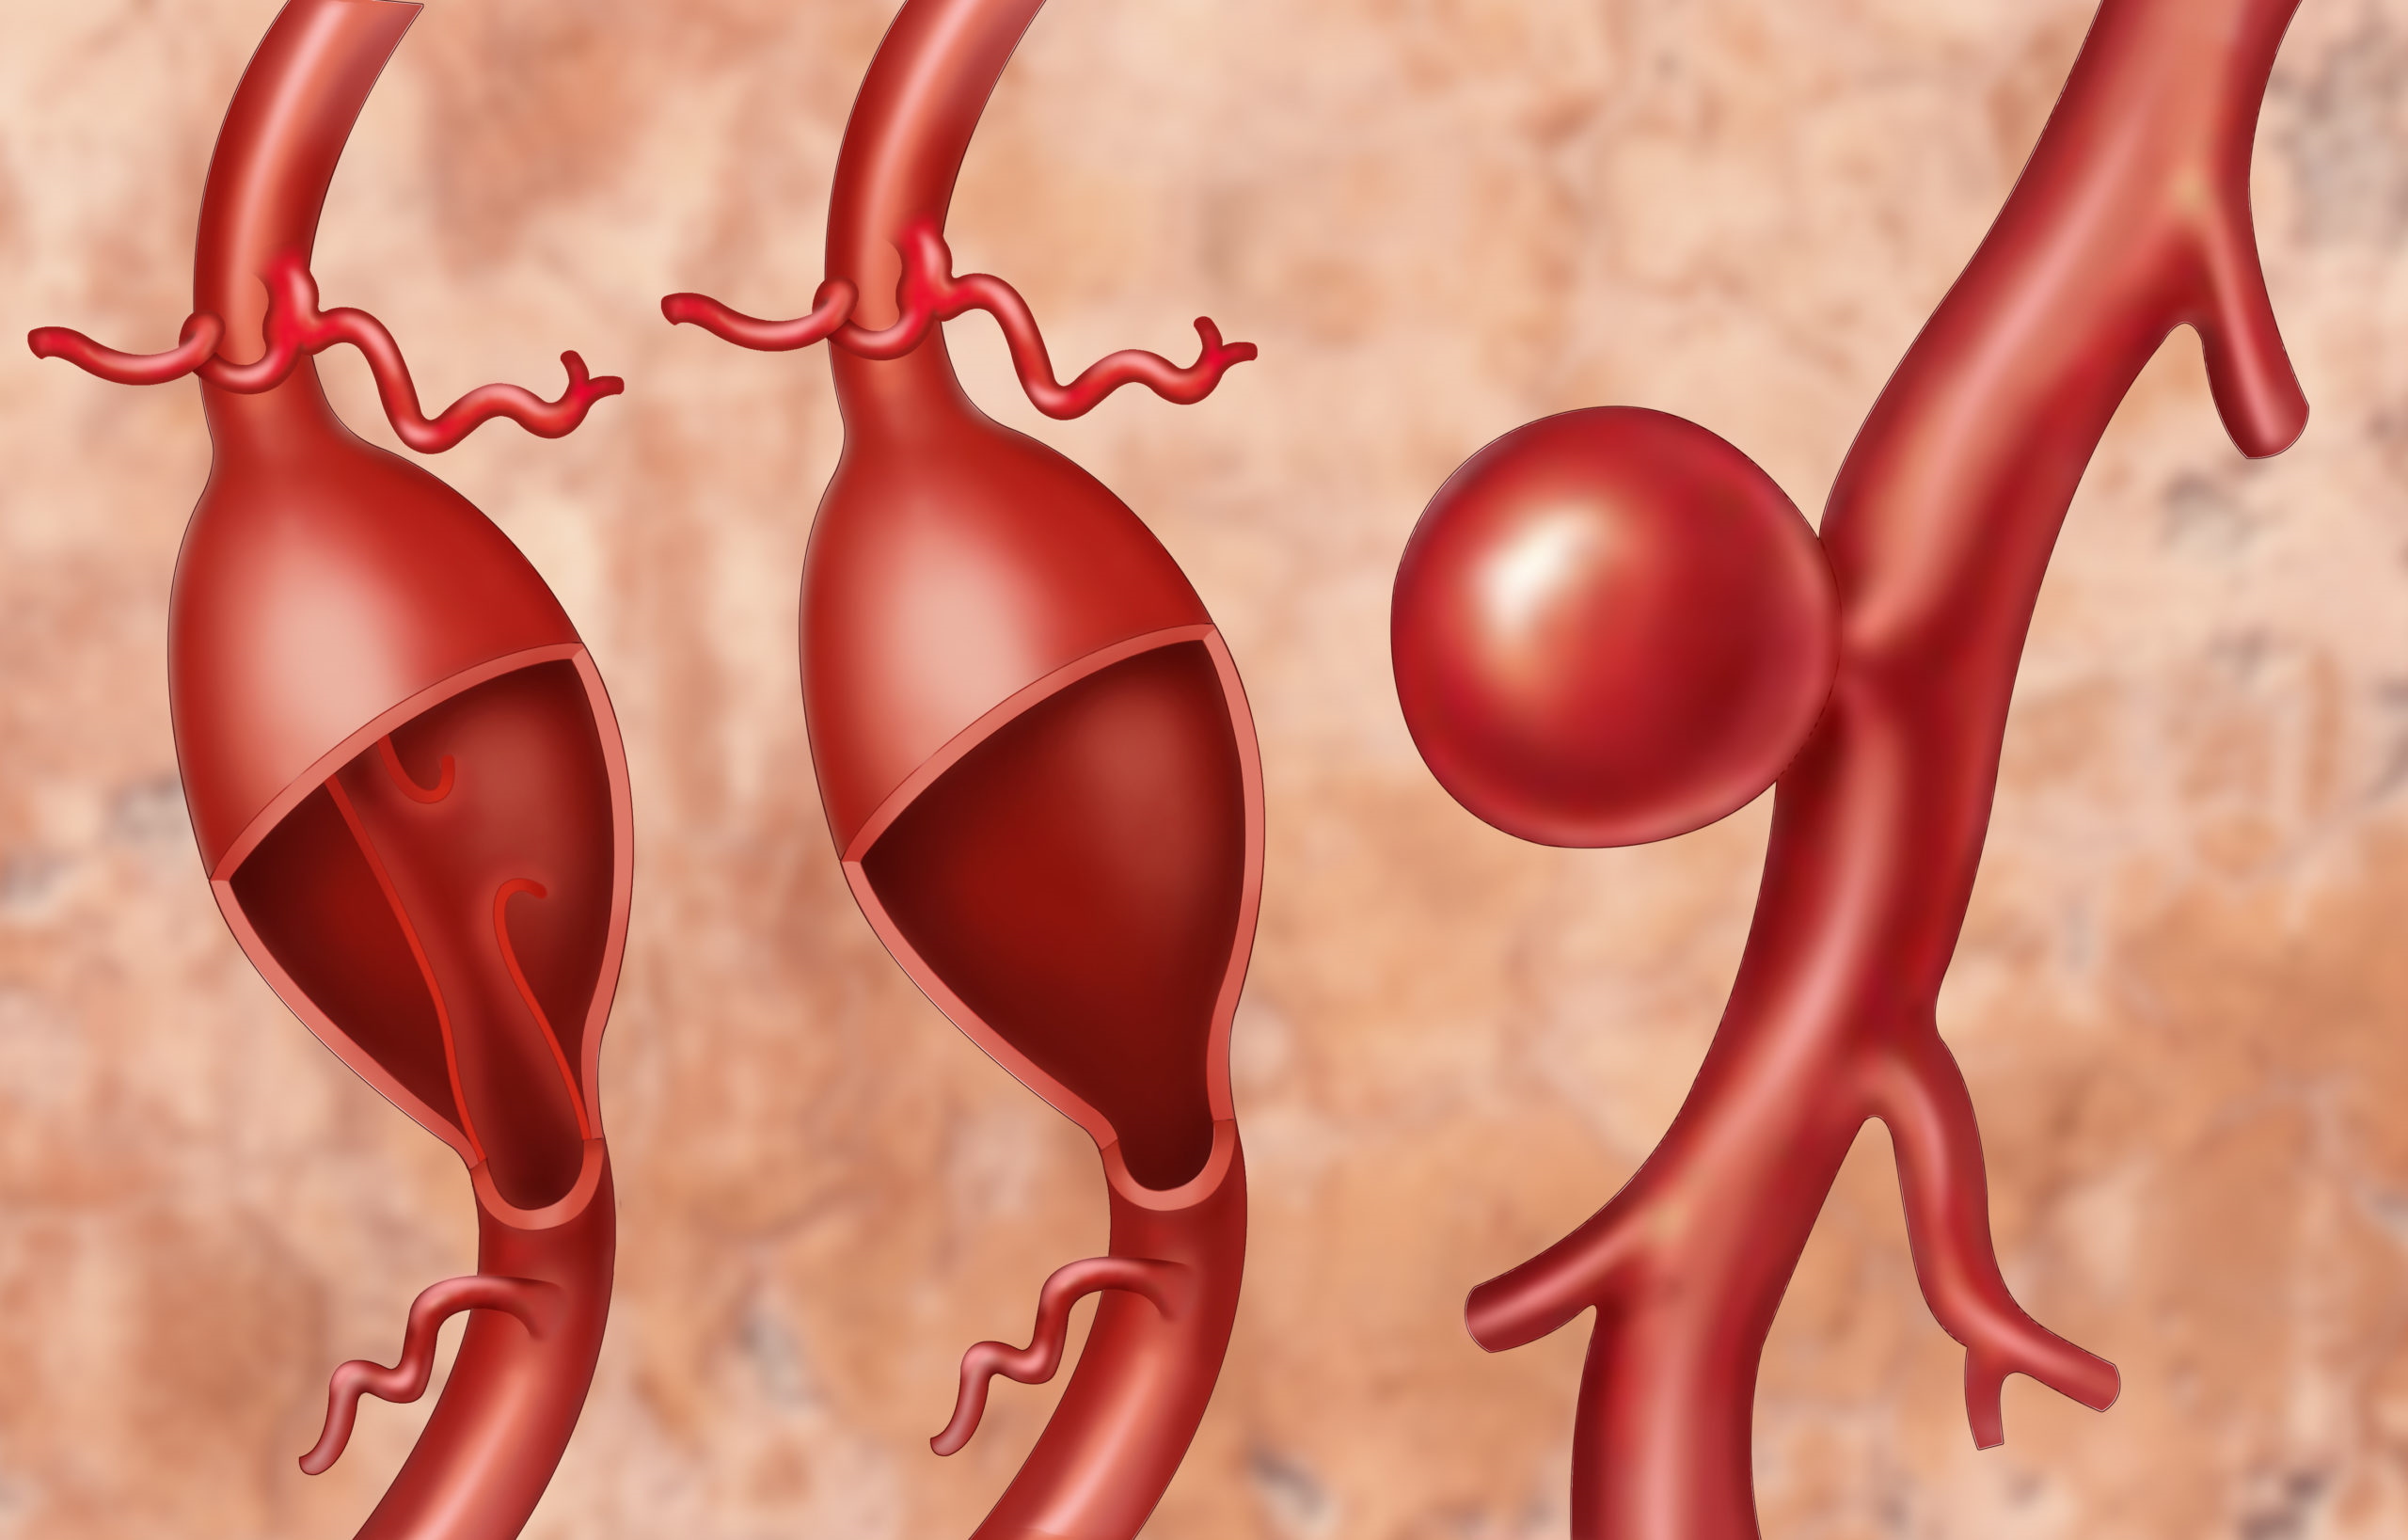

Снимки и иллюстрации микроаневризм сосудов головного мозга